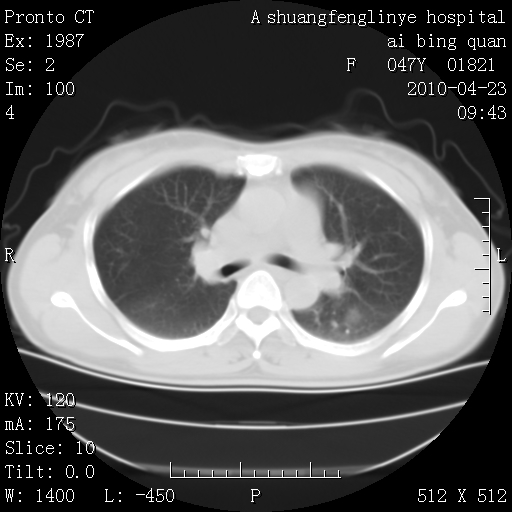

标题: CT25944:胸痛、气短、前几日高烧!肺Ca?请会诊! [打印本页]

标题: CT25944:胸痛、气短、前几日高烧!肺Ca?请会诊!

kaolv 周围型肺癌并同肺转移

双肺多发结节,考虑转移瘤,肺癌肺转移不除外

周围型肺癌并肺转移

双肺多发结节,部分密度较高,最大结节边缘光滑。临床有“胸痛、气短、前几日高烧”病史。首选考虑:右肺感染性病变!建议积极消炎后复查!

建议抗炎治疗后复查,排除肿瘤性病变。